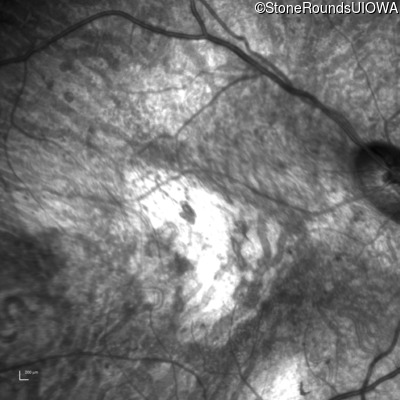

Infrared Fundus Photograph - Left - Hand Motion sc

Exemplar